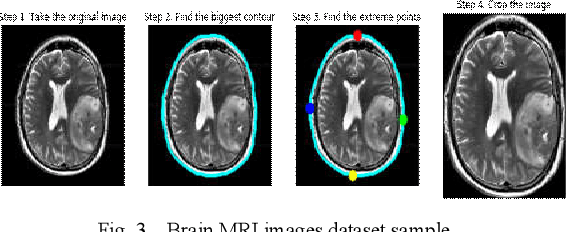

Abstract:Diagnosing Brain Tumor with the aid of Magnetic Resonance Imaging (MRI) has gained enormous prominence over the years, primarily in the field of medical science. Detection and/or partitioning of brain tumors solely with the aid of MR imaging is achieved at the cost of immense time and effort and demands a lot of expertise from engaged personnel. This substantiates the necessity of fabricating an autonomous model brain tumor diagnosis. Our work involves implementing a deep convolutional neural network (DCNN) for diagnosing brain tumors from MR images. The dataset used in this paper consists of 253 brain MR images where 155 images are reported to have tumors. Our model can single out the MR images with tumors with an overall accuracy of 96%. The model outperformed the existing conventional methods for the diagnosis of brain tumor in the test dataset (Precision = 0.93, Sensitivity = 1.00, and F1-score = 0.97). Moreover, the proposed model's average precision-recall score is 0.93, Cohen's Kappa 0.91, and AUC 0.95. Therefore, the proposed model can help clinical experts verify whether the patient has a brain tumor and, consequently, accelerate the treatment procedure.